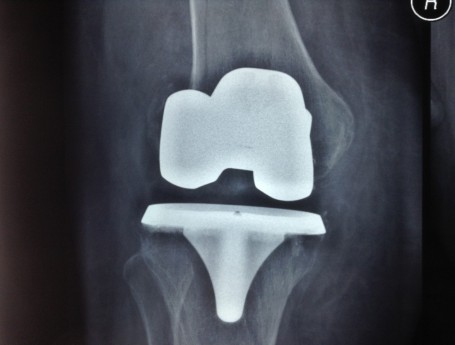

Revision Total Knee Replacement After a fructure

• Revision Total Knee Replacement After a fructure